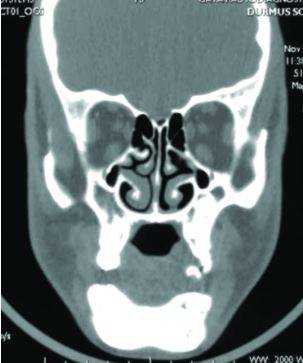

- Рентгенография челюсти. Рентгенологическое исследование - базовый метод диагностики пациентов с подозрением на остеонекроз челюсти. Визуальные изменения костной ткани включают реактивный периостальный остеогенез, уплотнение твердой пластинки альвеолы, утолщение дна верхнечелюстного синуса. С помощью рентгенографии также определяются очаги костной деструкции.

- МСКТ челюсти. На начальных стадиях процесса выявляются «пустые» костные лунки, очаги деструкции челюсти, уменьшение размера периодонтальной щели. Для поздней стадии остеонекроза характерен масштабный очаг деструкции, который выходит за границы альвеолярного отдела челюстной кости. Изредка определяются патологические переломы челюсти.

Рентген, а лучше КТ (компьютерная томография) помогает определить площадь патологического процесса, степень поражения, наличие переломов, секвестров (отмерших фрагментов кости, свободно лежащих между здоровых тканей).